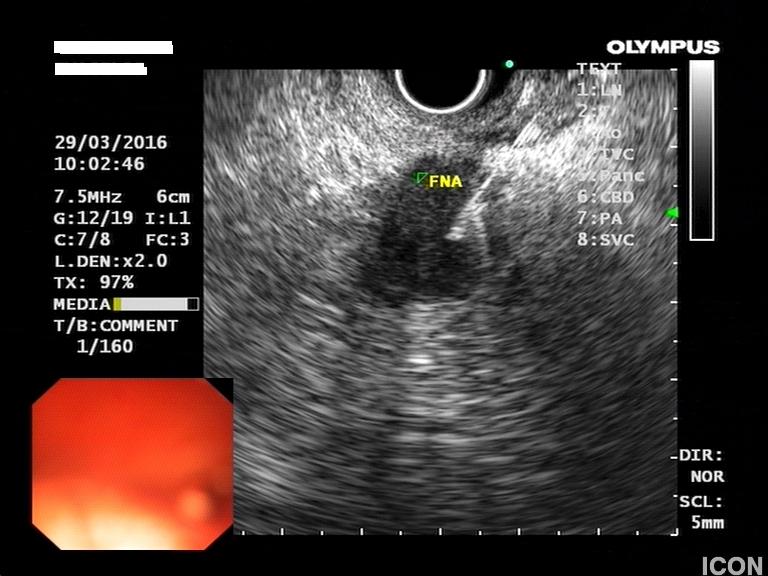

Ο ασθενής υποβλήθηκε σε ενδοσκοπικό υπέρηχο που έδειξε μια υποηχοϊκή μάζα διαμέτρου 21 χιλιοστών, με σαφή όρια, στην παγκρεατική κεφαλή και μεγάλη διάταση του χοληδόχου πόρου και του παγκρεατικού πόρου (διάμετρος 12 χιλιοστά).

Η μάζα είχε ξεκάθαρο διαχωριστικό όριο λίπους από την άνω μεσεντέριο φλέβα και δεν διηθούσε κανένα άλλο μεγάλο αγγείο της περιοχής (πυλαία φλέβα, σπληνοπυλαία συμβολή και αρτηρίες). Έγινε βιοψία με λεπτή βελόνη (FNA Χ3) και το κυτταρολογικό υλικό ήταν θετικό για αδενοκαρκίνωμα παγκρέατος. Το νεόπλασμα κρίθηκε χειρουργήσιμο και ο ασθενής υποβλήθηκε σε επέμβαση Whipple κατά την οποία αφαιρέθηκε πλήρως η παγκρεατική κεφαλή και ο όγκος σε υγιή όρια αλλά και 12 λεμφαδένες που ήταν όλοι αρνητικοί για κακοήθεια. Ο ασθενής υποβάλλεται σε συμπληρωματική χημειοθεραπεία.

Λήψη βιοψίας (FNA)